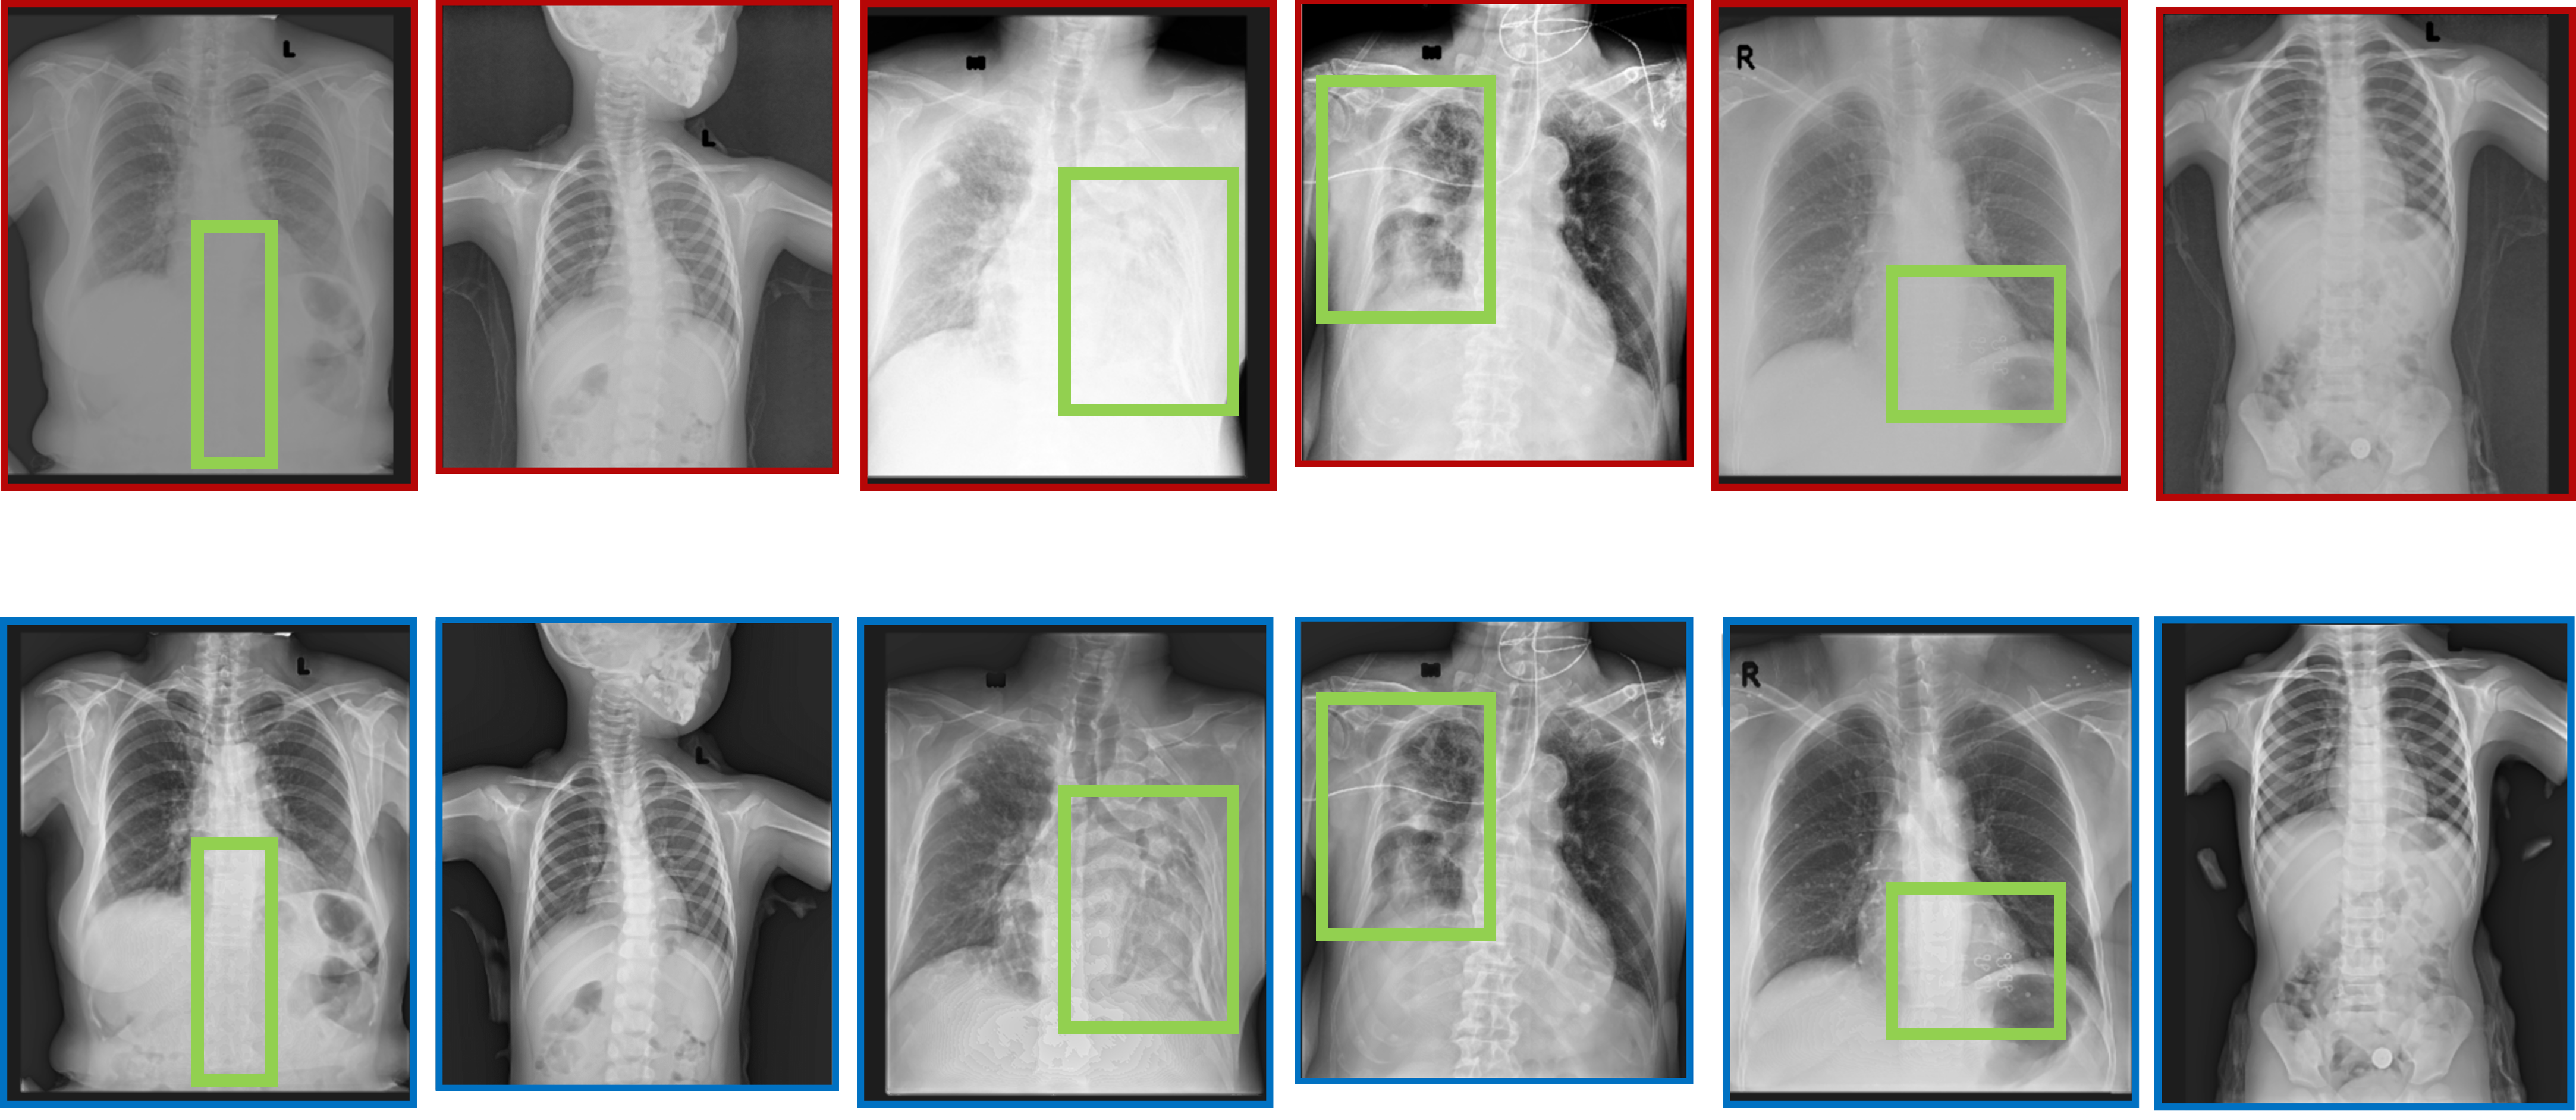

Medical images from different scanners often vary in texture and noise, complicating diagnosis. I developed Physics-Informed Deep Neural Networks that harmonize these images, making a scan from Scanner A look quantitatively identical to Scanner B.

• Generalizability: Unlike standard "black-box" AI, I injected physics constraints (noise power spectra, modulation transfer functions) into the training process and model architecture. This ensured the model learned the underlying physics of image formation, not just dataset correlations.

• Mojtaba Zarei, et al., "A probabilistic conditional adversarial neural network to reduce imaging variation in radiography," SPIE Medical Imaging (Best Poster Award), 2021.

Figure: Comparison of clinical harmonized and non-harmonized CXRs images generated by a physics-informed GAN trained solely on digital twin data.